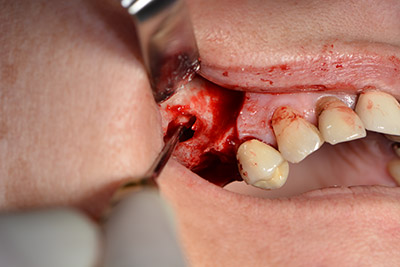

Die 59-jährige Patientin wurde mit einer fortgeschrittenen Parodontitis vorstellig, beschrieb ein ungutes Gefühl und einen schlechten Geschmack ausgehend vom ersten Quadranten distal. Die klinische Untersuchung zeigte allgemein erhöhte Taschentiefen und einen stark fortgeschrittenen Knochenabbau in regio 16 und 14. Die radiologische Untersuchung untermauerte den Befund (Abb. 1). Die Zähne 16 und 14 waren nicht zu erhalten.

Abb.1: Orthopantomogramm mit Knochenabbau in Regio 16–14.*